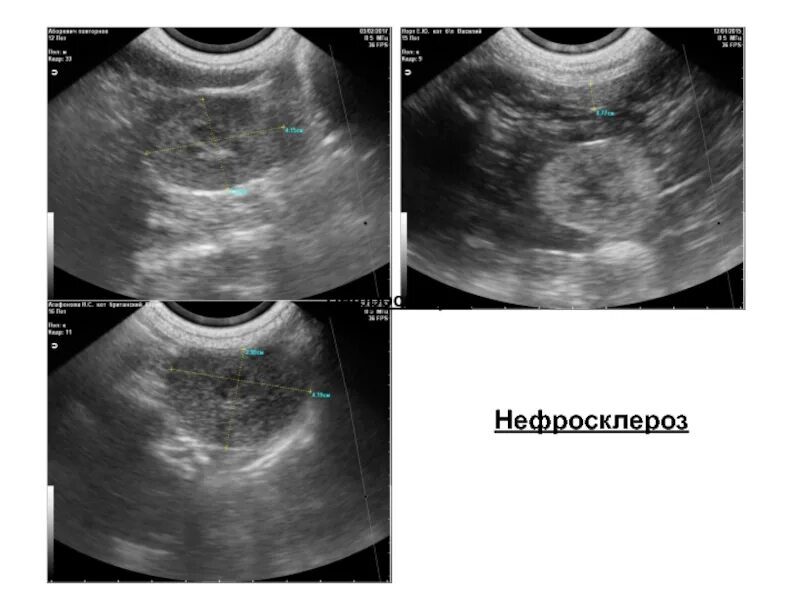

Нефросклероз почек на узи что это такое